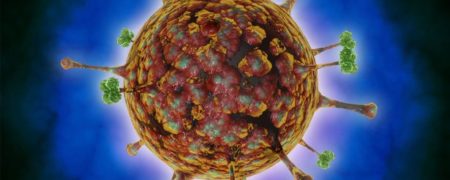

پزشکان در چین زنگ خطر بروز یک ویروس تازه شناساییشده را به صدا درآوردهاند. ویروس لانگیا (langya) تاکنون ۳۵ نفر را در دو استان در شرق چین آلوده کرده است.

ویروس...

شیوع ویروس جدید «لانگیا» باز هم در چین؛ آیا همه گیری بزرگ دیگری در راه است؟